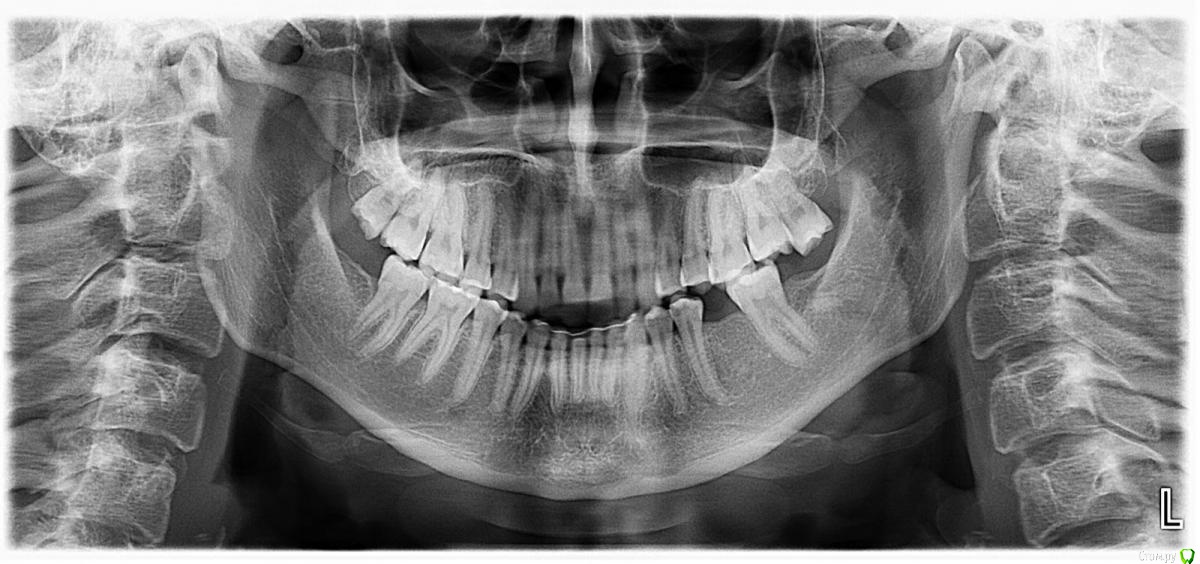

Lyubanya Опубликовано 15 октября, 2019 Поделиться Опубликовано 15 октября, 2019 Доброго дня, коллеги. Хотелось бы установить имплант в область отсутствующего 36 зуба. Носила брекеты ранее, все зубы в правильном прикусе, только 26 немного опустилась, 37 наклонился. Беспокоит что места для коронки вроде как маловато, можно ли обойтись без ортодонтии? Ссылка на комментарий

krokomot Опубликовано 15 октября, 2019 Поделиться Опубликовано 15 октября, 2019 Доброго дня, коллеги. Хотелось бы установить имплант в область отсутствующего 36 зуба. Носила брекеты ранее, все зубы в правильном прикусе, только 26 немного опустилась, 37 наклонился. Беспокоит что места для коронки вроде как маловато, можно ли обойтись без ортодонтии? Вполне можно обойтись без фиксации бреккетов, а обойтись локальнм перемещением 3.7 дистально на миниимплантате или на основном имплантате и коронке и интрузии 2.6 1 Ссылка на комментарий

колесников Опубликовано 17 октября, 2019 Поделиться Опубликовано 17 октября, 2019 С десной и антагонистом поработать,можно имплантировать Ссылка на комментарий